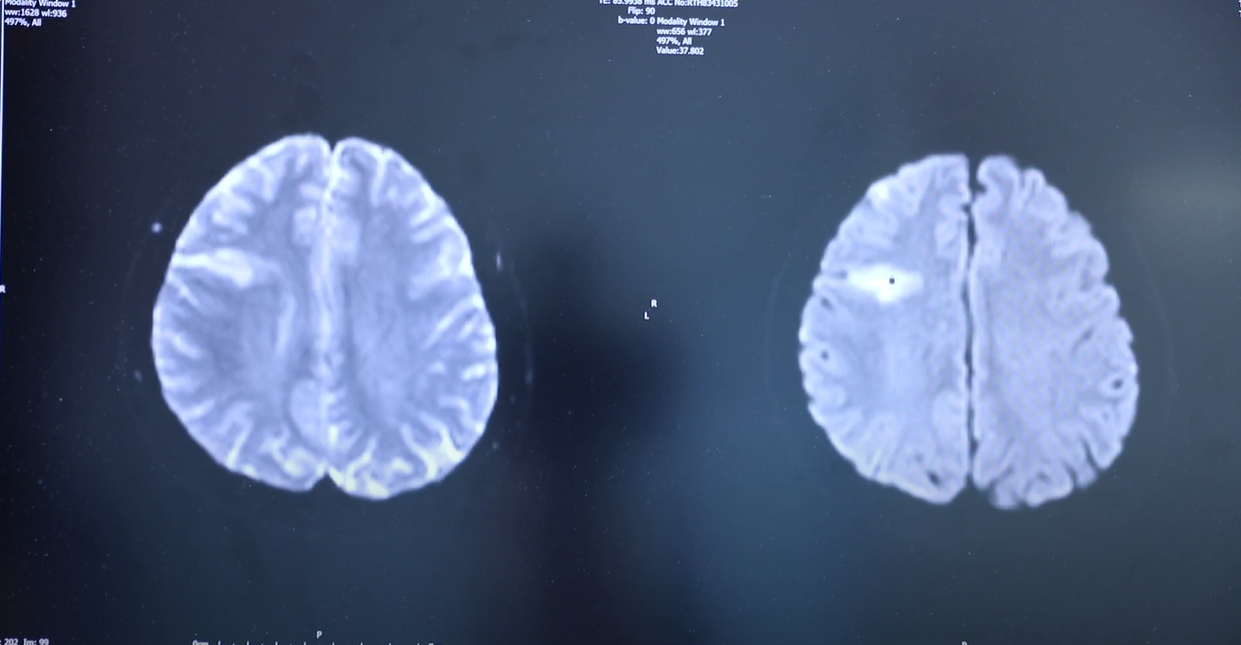

She has also set up the Thames Valley Young Stroke Study, a regional study which takes a deeper look at younger stroke patients. “It is fully phenotyped, meaning all patients undergo not just standard investigations but also more detailed imaging of their vessels, heart, and brain,” says Linxin.